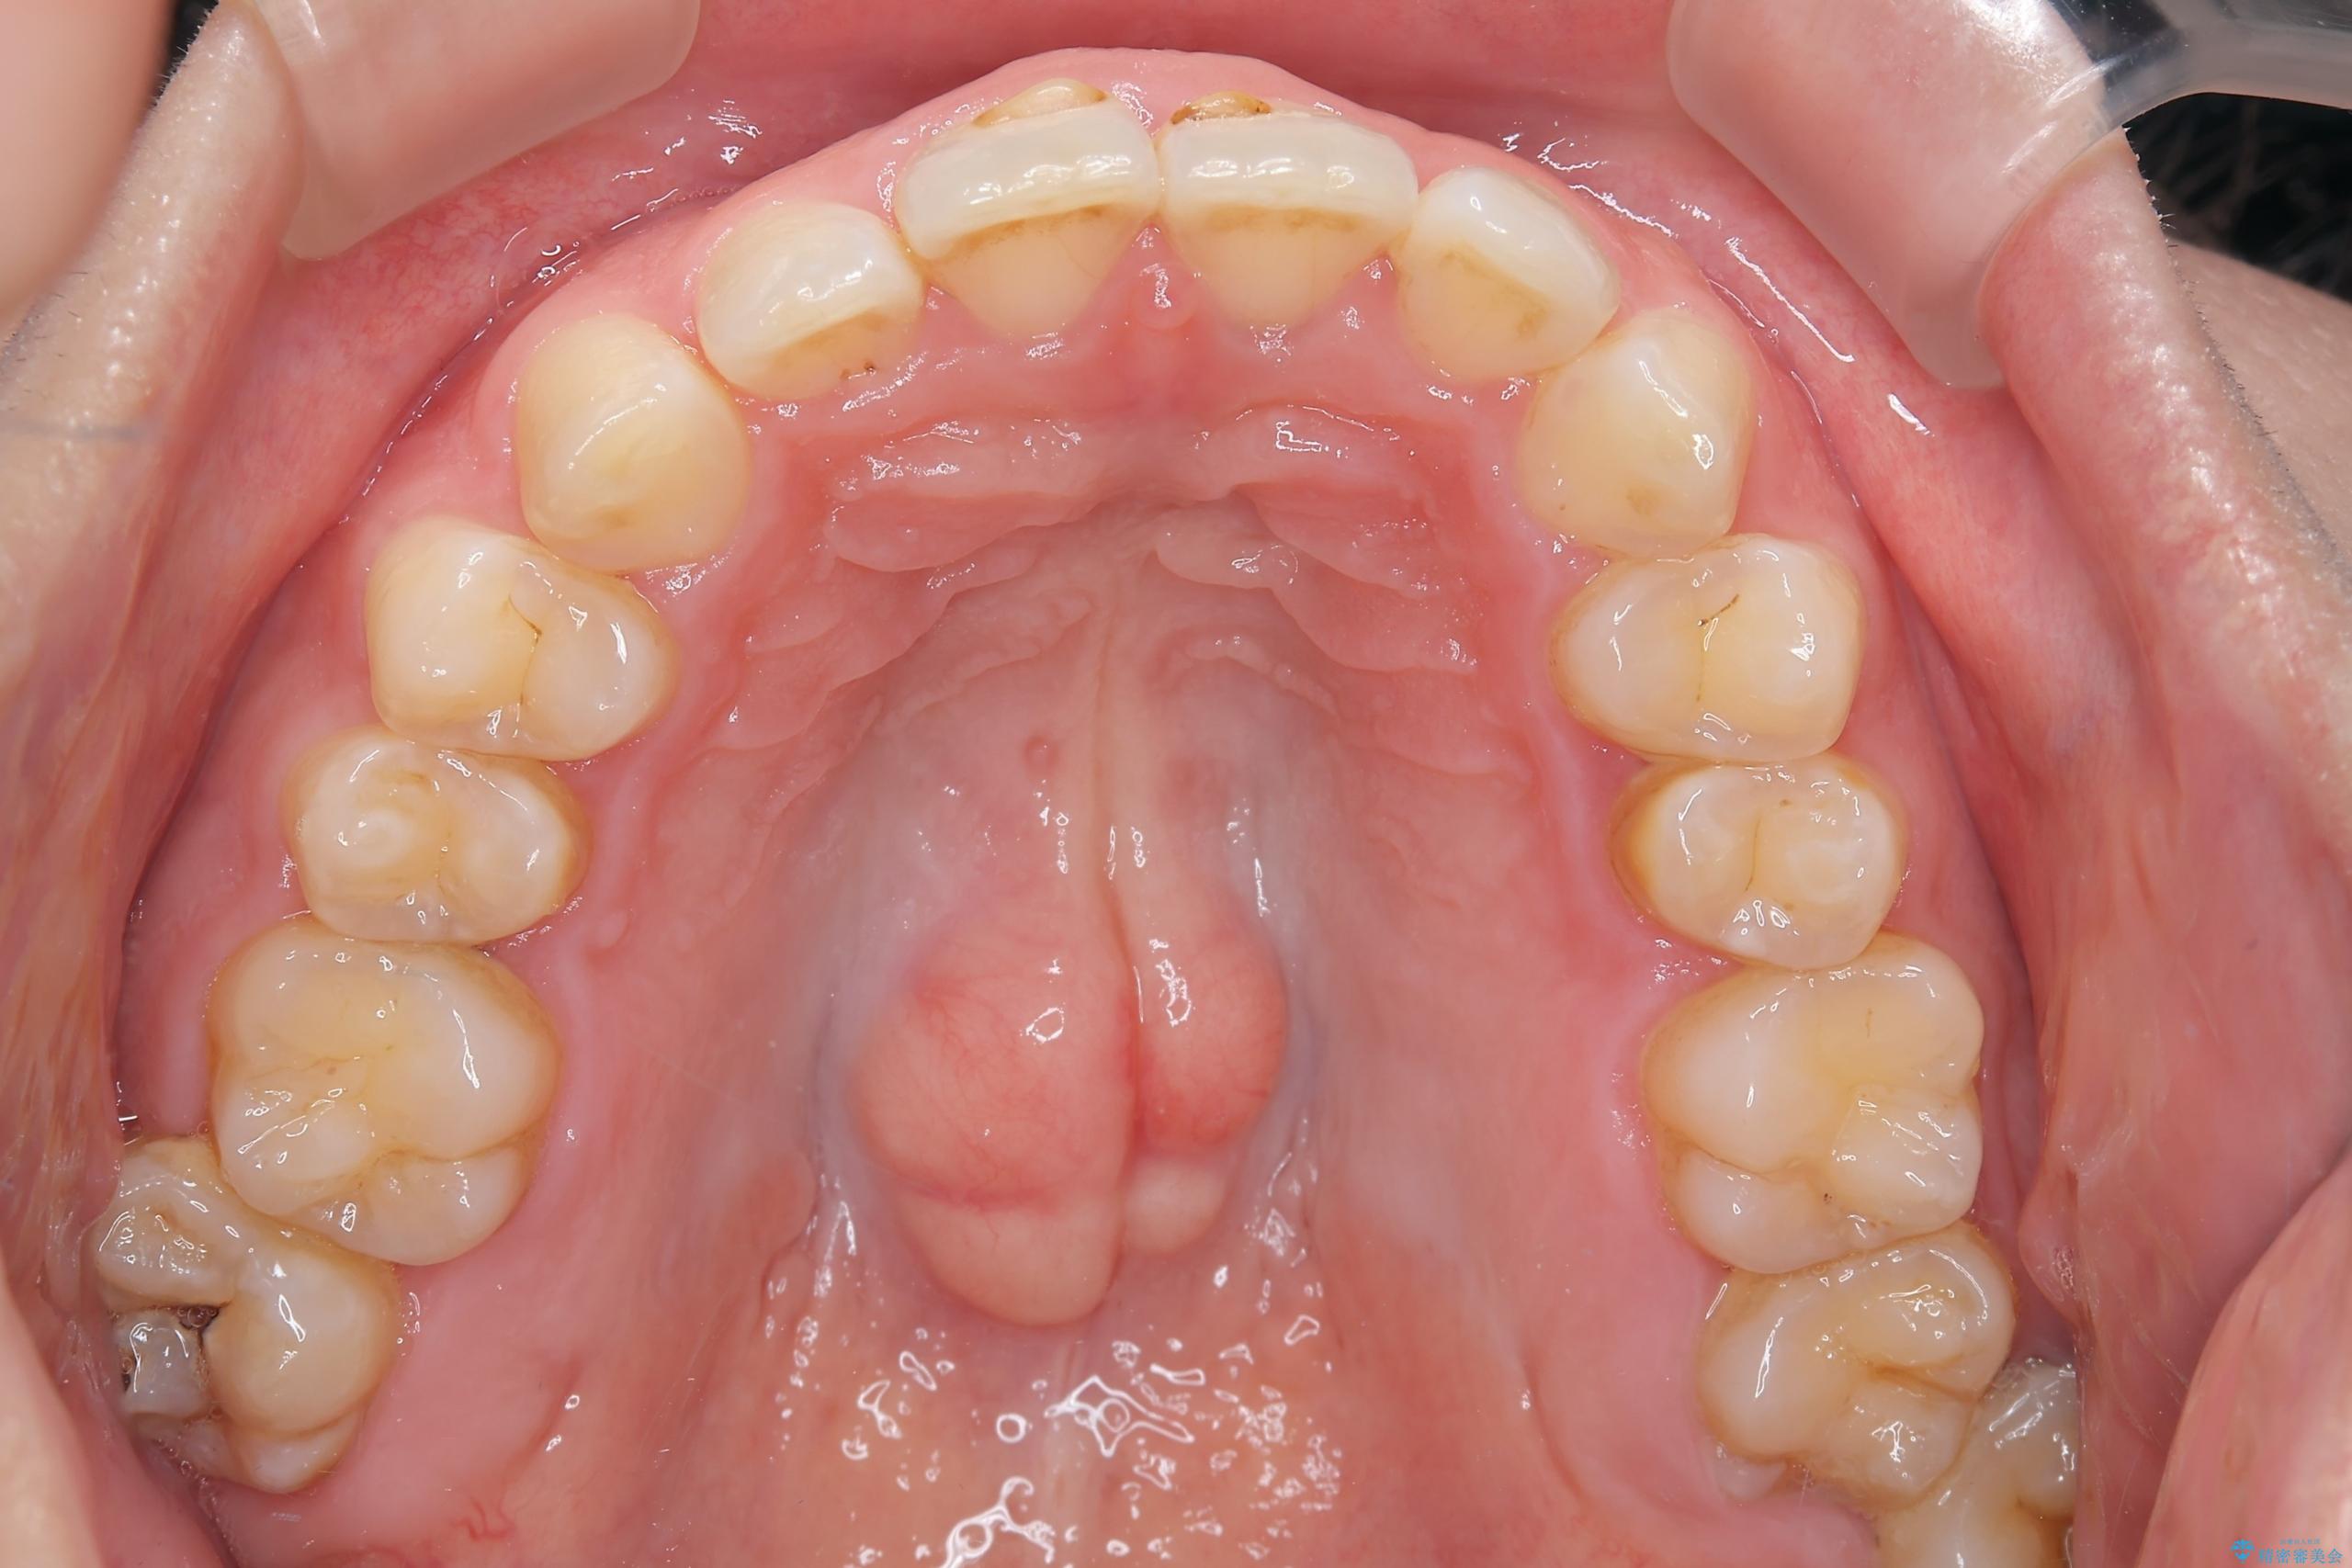

- 下の歯のがたつきを主訴に来院されました。

下の歯のがたつきと右の奥歯の噛みあわせ改善するために治療計画を立てることにしました。

右側臼歯部の咬合改善のために、臼歯部のみ部分的なワイヤー矯正を行い、咬合改善がみられてからインビザラインにて全体的な矯正を行なっていく治療計画を立てました。